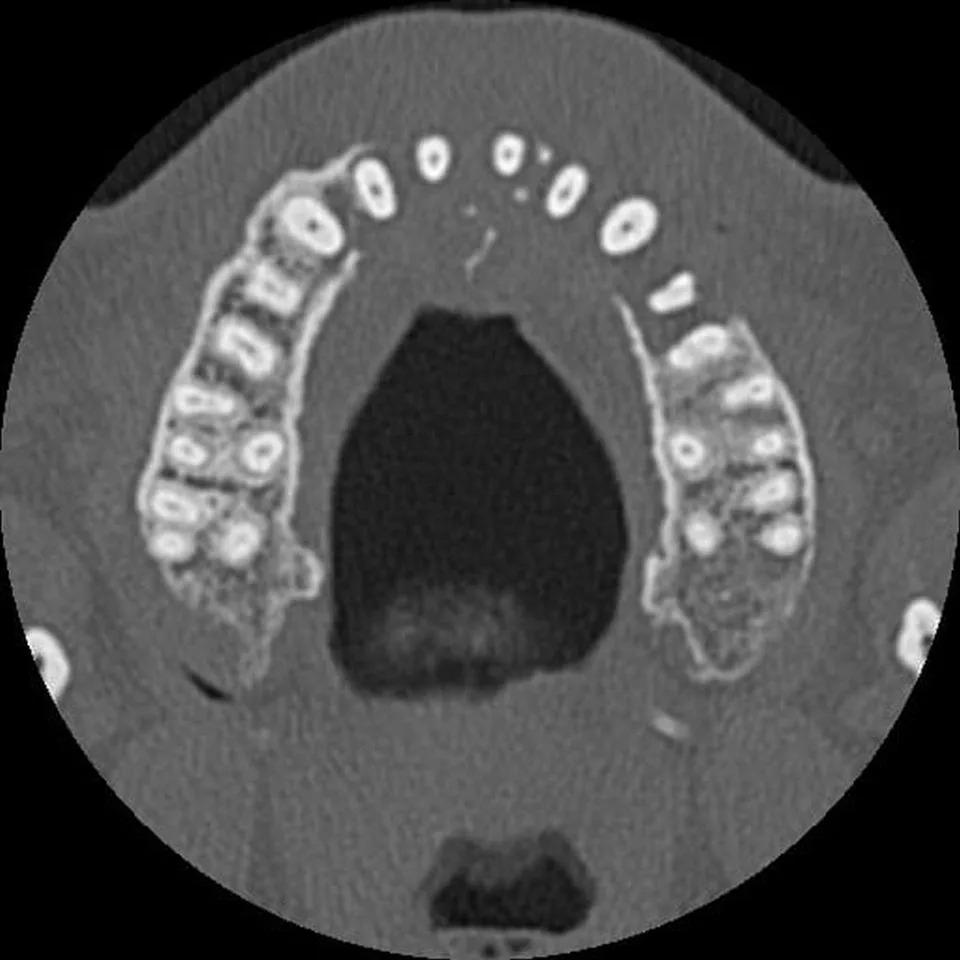

After returning home, Vieira visited his local dentist. The dentist took X-rays of his teeth as a part of standard protocol, but was immediately stunned when viewing his scans.

“The scan revealed a large mass inside the front left of his face, and surrounding bone had disappeared,” his wife Mandy, 44, said in a GoFundMe post.

Edd Vieira’s scans

Credit: Kennedy News & Media